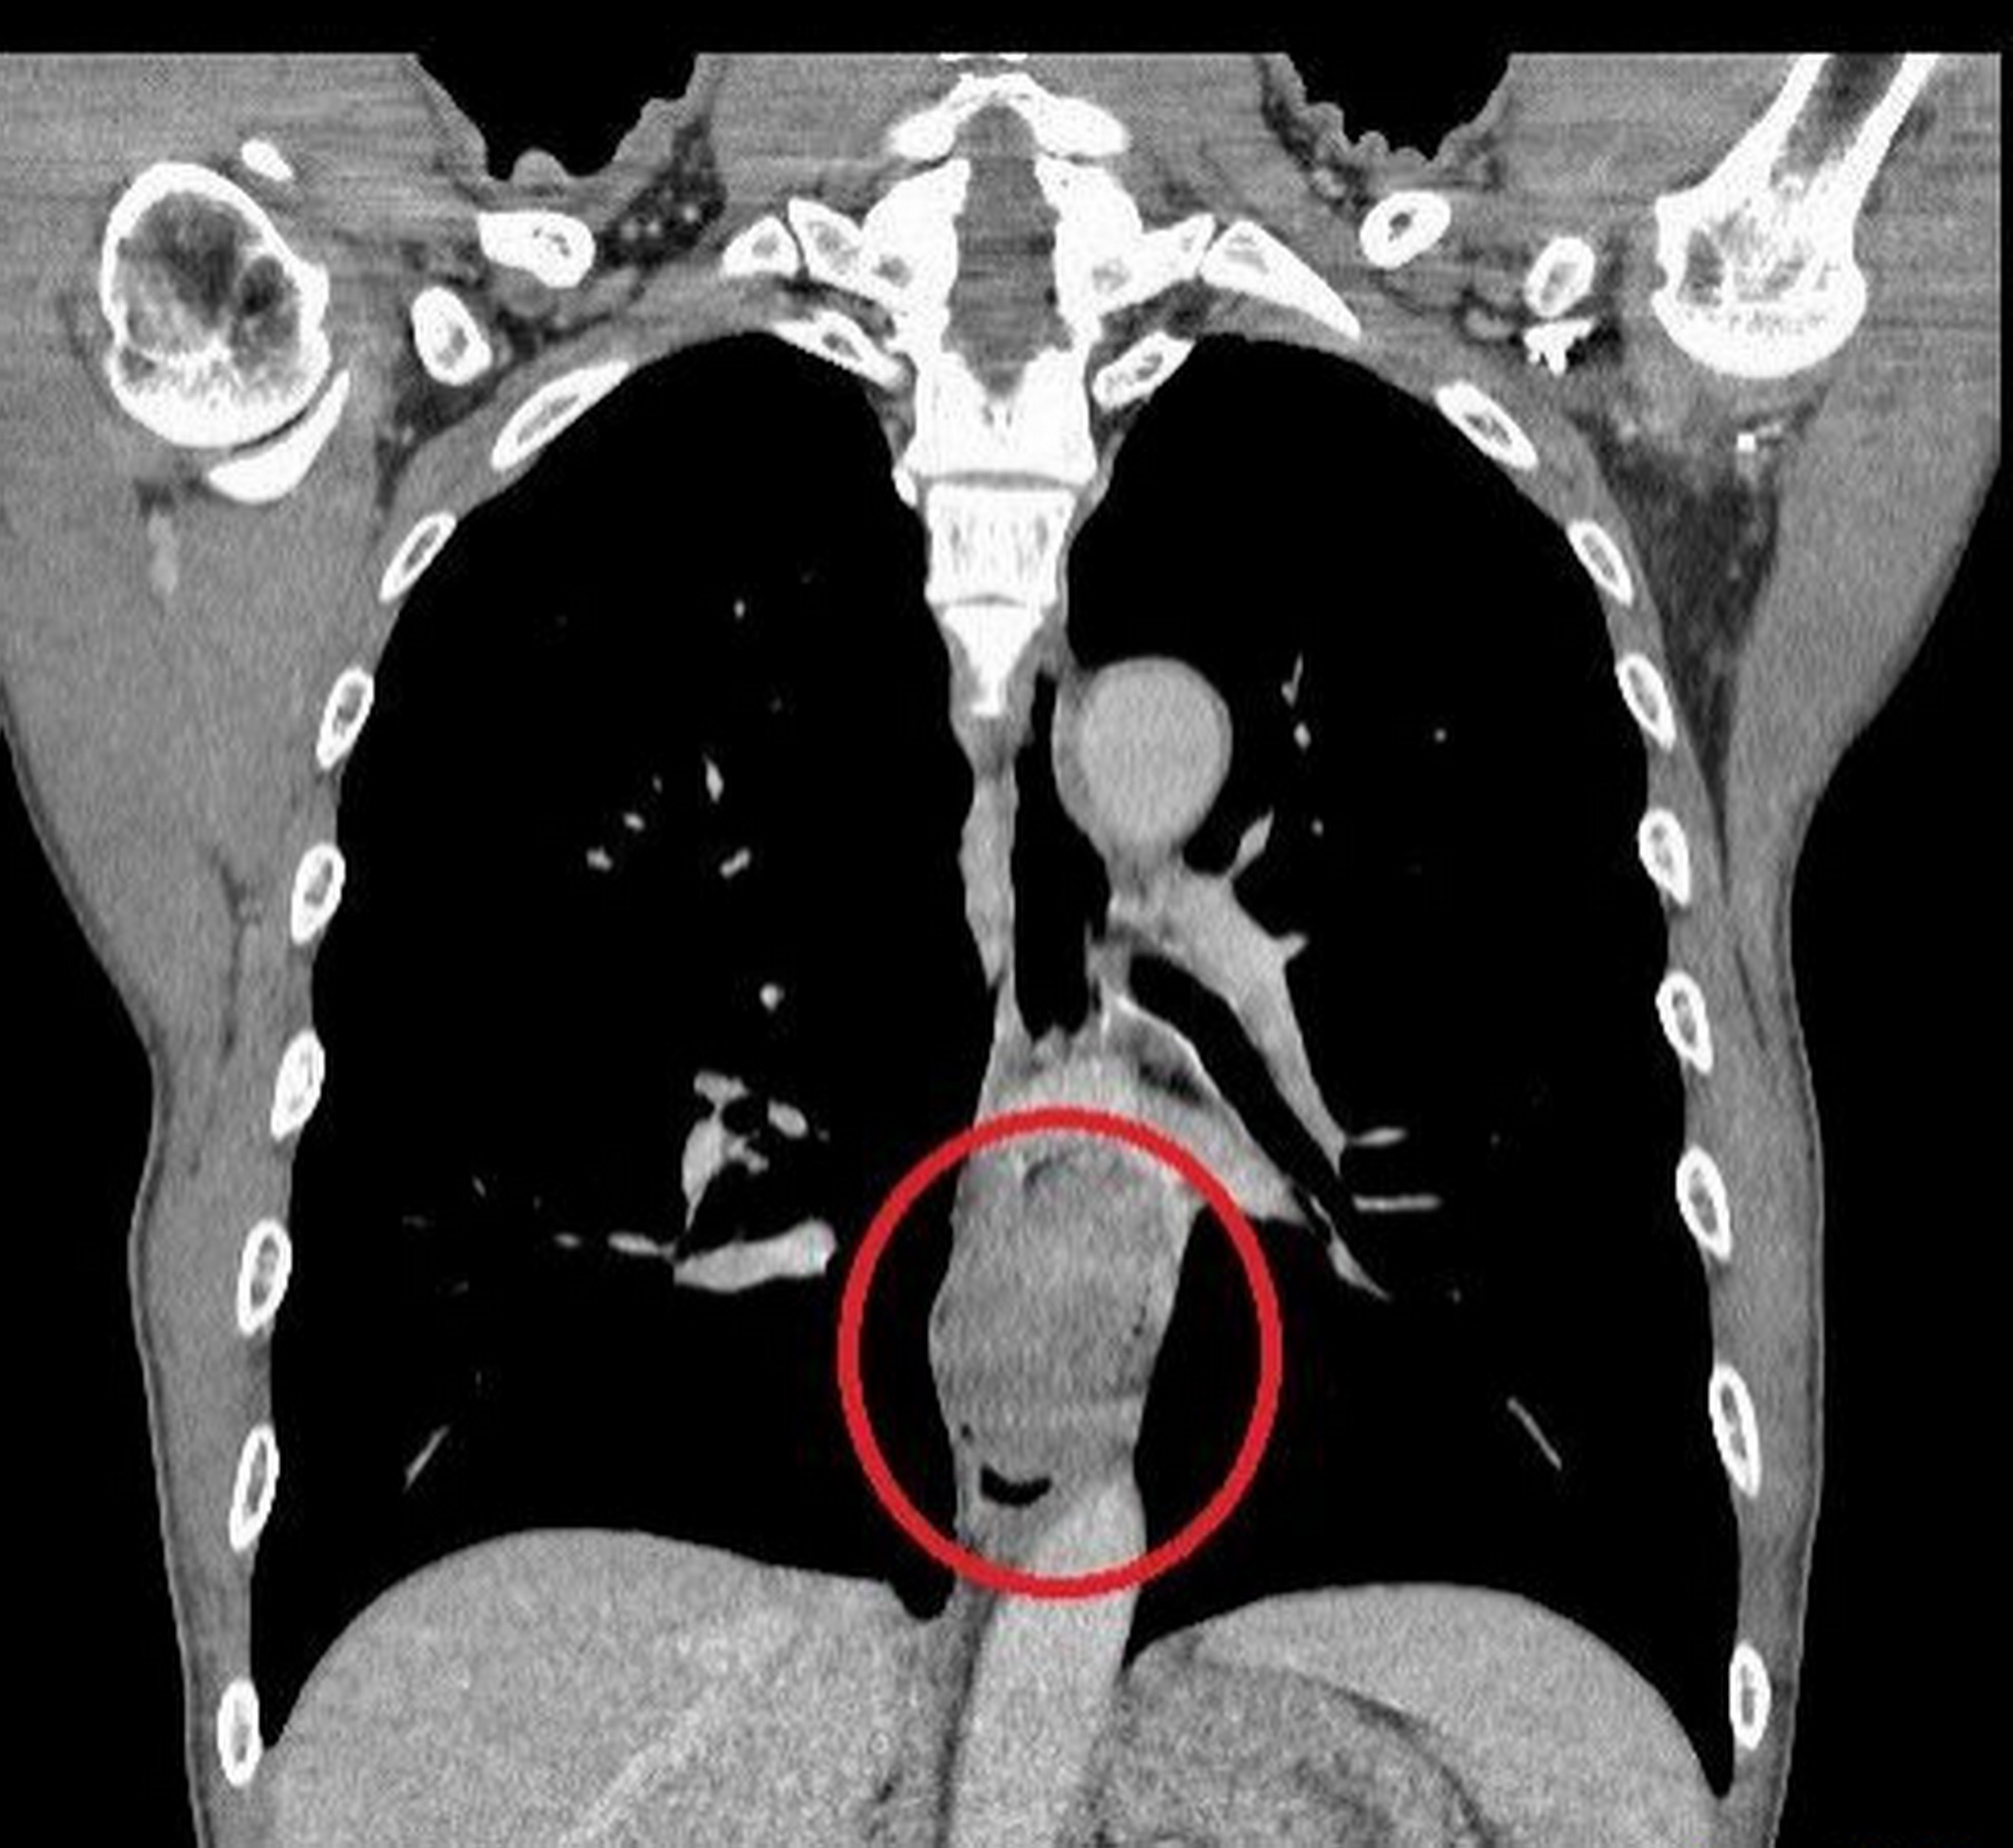

劉柏毅表示,達文西食道切除暨胃管重建手術僅需透過數個約1~2公分的小傷口即可完成,藉由3D立體內視鏡與機械手臂切除食道腫瘤、清掃縱膈腔淋巴,清晰視野下可避開控制聲帶與吞嚥的重要神經,減少出血與神經損傷風險。